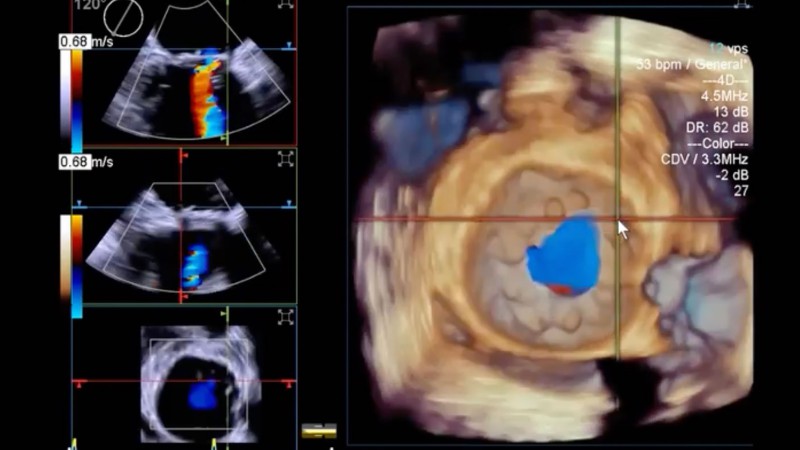

- اکوکاردیوگرافی (اکو قلبی): استفاده از امواج فراصوت برای دیدن دهلیزه، بطن ها، دریچه ها و دیواره های قلبی. شبیه انجام سونوگرافی در نقاط دیگر بدن. با اکوکاردیوگرافی داپلِر، جریان خون در نقاط مختلف قلب اندازه گیری می شود. ارزیابی قدرت انقباض یا پمپاژ قلب از دیگر کابردهای ای روش تشخیصی است.